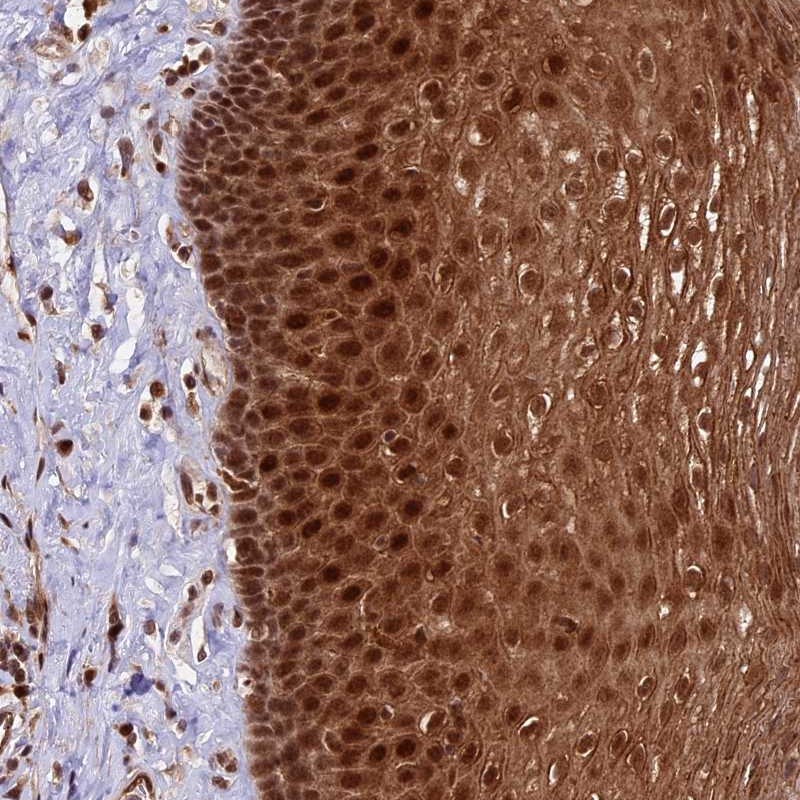

Immunohistochemical staining of human esophagus shows strong cytoplasmic and nuclear positivity in squamous epithelial cells.